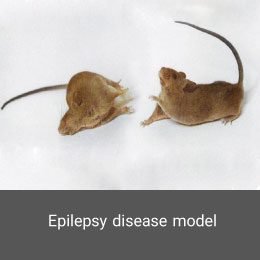

- Create and induce a variety of animal models